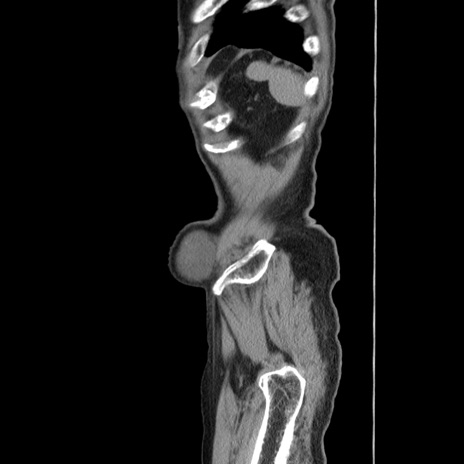

症例24(矢状断像)

【症例】80歳代男性

【主訴】左側腹部痛、嘔吐

【現病歴】本日早朝より左腹部に痛みあり。昼頃嘔吐認めたため、救急要請。

【既往歴】直腸癌(Mile手術)、胆摘

【身体所見】意識清明、BT 35.9℃、BP 221/93mmHg、SpO2 97%(RA) 、腹部:左ストーマ周囲に限局性の腹部膨隆あり。 膨隆部自発痛・圧痛あり・軟。

【データ】WBC 7700、CRP 0.09